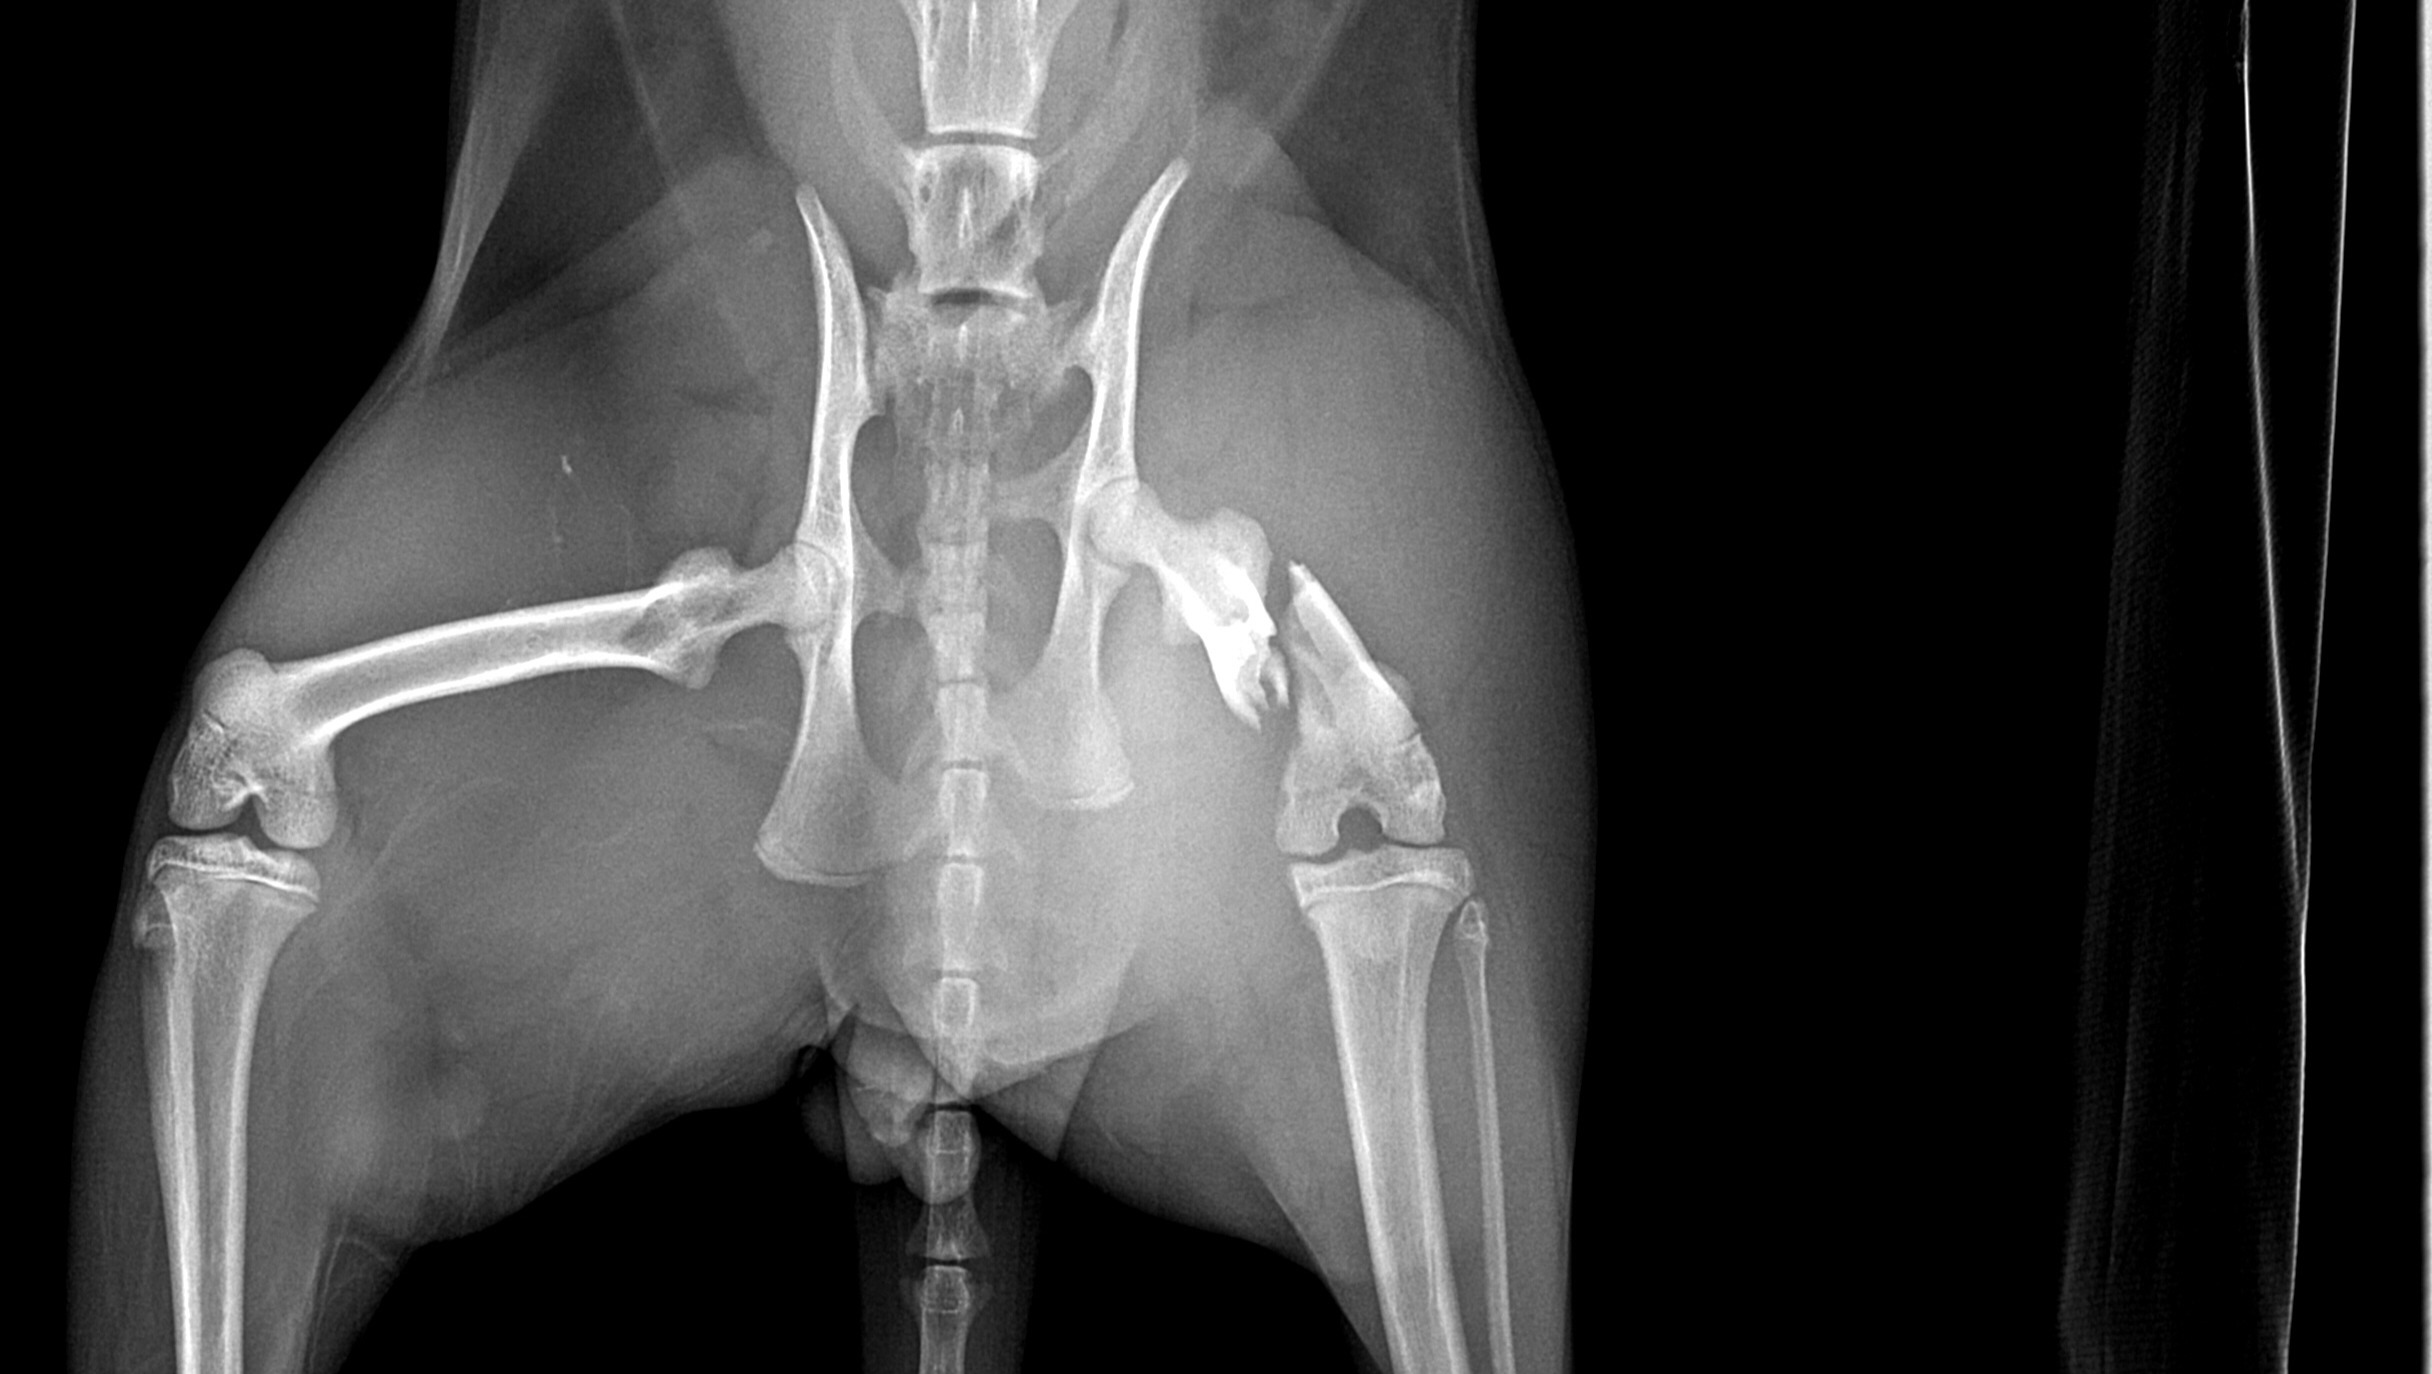

Our sweet angel of a kitten is seriously injured. His name is Nugget, he is an orange tabby and he is 7 months old. We found out that his pelvis was snapped in half, and his femur was shattered. He was likely hit by a car or was trapped by an animal that pulled his leg. He is going to need surgery to walk again, but we can't afford to save him. We want to help him as much as we can, but are struggling to support his healing journey. Please help bring our baby home safely!

His checkups, bloodwork, x-rays, and prognosis have come out to a total of 1,620, and his surgery was quoted for 3,800.